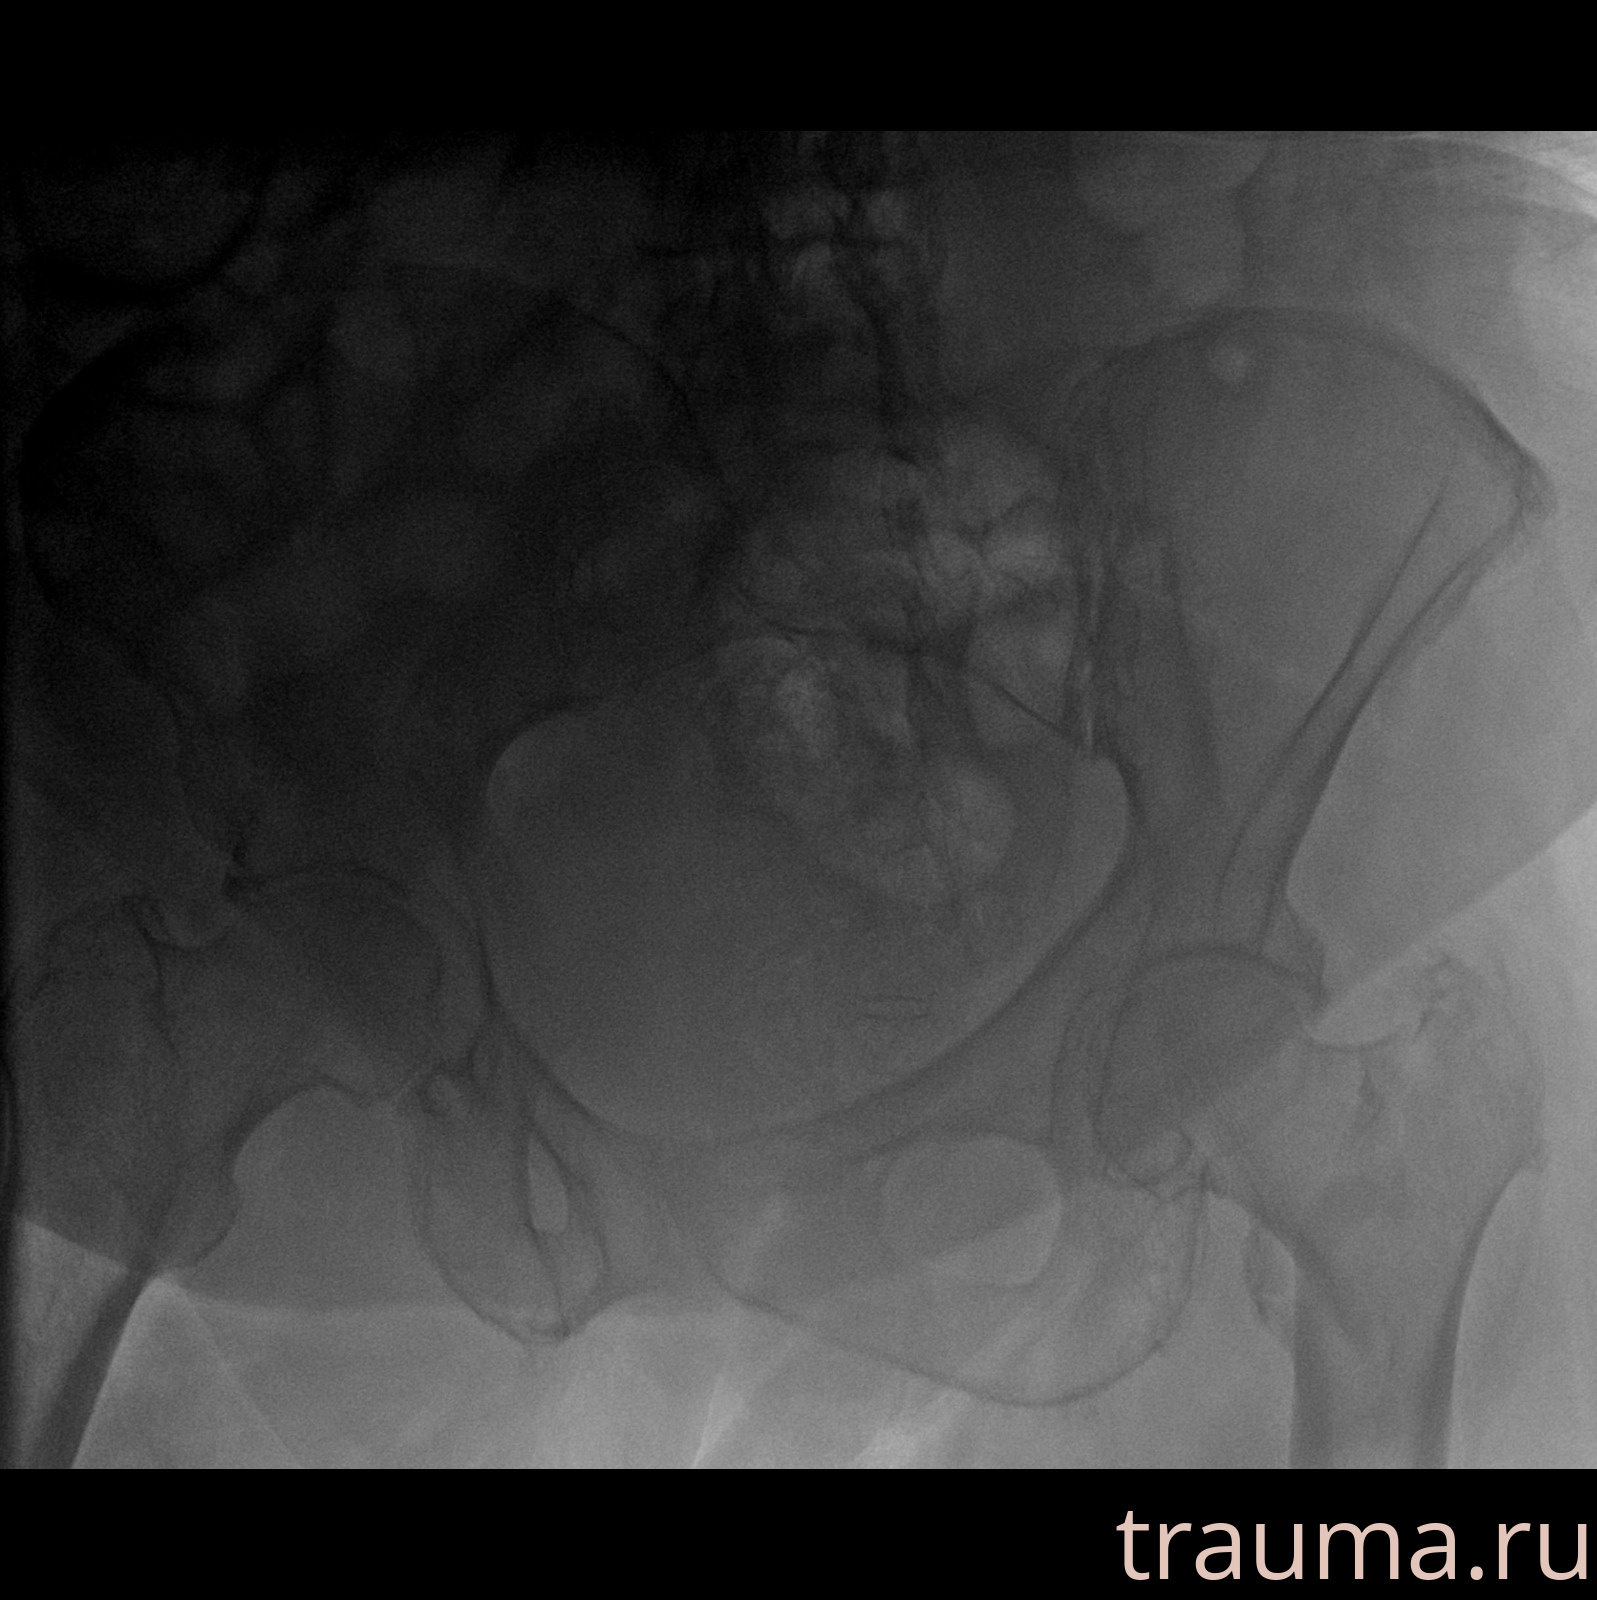

Рентген на дому: по вашему адресу приезжает врач-рентгенолог, травматолог-ортопед с мобильным рентгеновским аппаратом, проводит диагностику травмы или заболевания, делает необходимые рентгенограммы, дает рекомендации по дальнейшему лечению. Получить качественные снимки в домашних условиях возможно благодаря уникальной методике, разработанной МосРентген Центром для института  Склифосовского